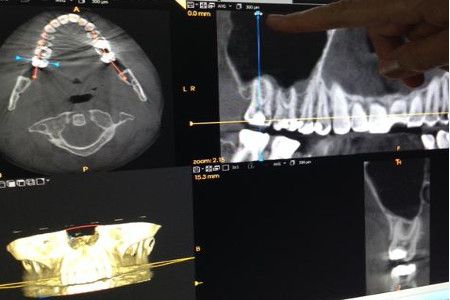

Dentaire

En savoir plus